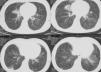

Una mujer de 26 años de edad presentaba tos, esputo, disnea de esfuerzo, pérdida de apetito, sudoración nocturna y pérdida de peso. La tos y la disnea por esfuerzo comenzaron hacía 6 años. El esputo, la pérdida de apetito y de peso aparecieron un año antes de acudir a nuestra consulta. En su historial clínico, se notificaba que había sido tratada por tuberculosis un año atrás. El diagnóstico de tuberculosis fue realizado en base a los síntomas y al estudio radiológico. Como los síntomas y los hallazgos radiológicos no respondieron a un tratamiento no específico, se diagnosticó tuberculosis por los síntomas y los resultados radiológicos. Durante el tratamiento contra la tuberculosis sus dolencias no se resolvieron del todo. Cuando sus síntomas se agravaron, solicitó asistencia en nuestra consulta externa. Tras las pruebas rutinarias, se realizó una TC. Se observó bronquiectasia en el lóbulo medio derecho y en el izquierdo inferior, así como densidad reticulonodular predominantemente en el lóbulo inferior de ambos pulmones. También se observó que existía conservación subpleural de estas lesiones (fig. 1). Fue hospitalizada y se le administró un tratamiento con antibióticos, debido al esputo purulento y a la fiebre. Después del tratamiento, se le aconsejó la realización de una broncoscopia, pero la paciente rehusó.

El hallazgo radiológico típico en pacientes con fibrosis pulmonar idiopática es la opacidad reticular periférica con predominio en las bases pulmonares. En algunos casos, las características en la TC de la NII pueden solapar aquellas más habituales en la neumonía intersticial de tipo usual (NIU). Como en la NIU, las anormalidades en la NII predominan generalmente en los segmentos medios e inferiores del pulmón. Sin embargo, existen menos probabilidades de que se produzca una distribución subpleural en la NII que en la NIU; de hecho, la ausencia de afectación subpleural conduce a una marcada preferencia por la NII3. En nuestro caso, las lesiones estaban localizadas predominantemente en el lóbulo inferior y, además, se observó preservación subpleural de las mismas.